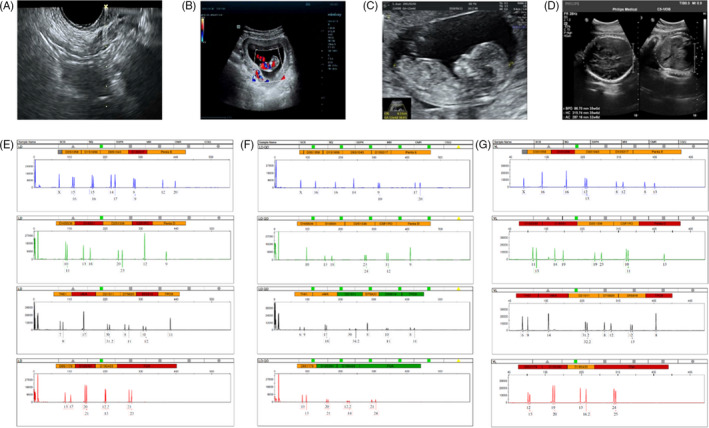

收集了15名接受取卵的患者的基本特征,包括取卵周期、胚胎移植和妊娠次數(shù)。一般來說,四個(gè)胎兒沒有出生缺陷,三個(gè)胚胎來自ICSI的受精類型,而最后一個(gè)是自然受孕的。1例術(shù)中超聲掃描顯示,在經(jīng)陰道超聲(TVUS)引導(dǎo)下,卵巢未見間質(zhì)增生或其他異常卵巢結(jié)構(gòu)(圖2A)。這名婦女在體外受精后成功懷孕,并在第8周進(jìn)行了基本產(chǎn)前程序的超聲掃描(圖2B),第13周(圖2C) 和第32周 (圖二維) 顯示正常的胎兒發(fā)育。微衛(wèi)星位點(diǎn)分析顯示,胎兒(圖2F)與母親有遺傳關(guān)系(圖2E) 供體UCMSC以外的其他人(圖2G)。